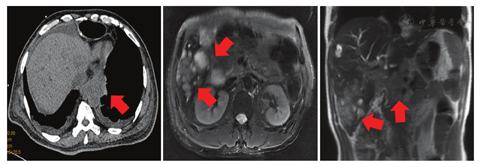

术后ECOG PS评分为1分,因患者拒绝静脉化疗,2018年8月10日至2018年9月21日术后外院行替吉奥60 mg每天早、晚餐后半小时口服,连续口服14 d,每21天为一周期,共化疗2个周期。2018年10月23日复查全身PET-CT示:右侧锁骨上、右侧颈部Ⅳ区、右侧颈部喉返神经旁、降主动脉旁、脾动脉近端近腹腔干多发淋巴结转移,肝S5转移。患者未行治疗。1个月后胸腹盆CT提示降主动脉旁淋巴结转移灶及肝转移灶较前增大(见图1),予紫杉醇脂质体270 mg第1天静脉滴注+顺铂50 mg第1天、40 mg第2~3天静脉滴注,每21天为一周期,共化疗2个周期,2个周期后评价疗效为疾病进展(见图2)。程序性细胞死亡配体1(PD-L1)检测(原手术组织,抗体型号22C3)结果为高表达,肿瘤细胞阳性比例分数(TPS)为80%。2019年2月15日给予帕博利珠单抗注射液200 mg第1天+伊立替康400 mg第2天,每21天为一周期,治疗1个周期。1周后患者出现黄疸,肝功能示:丙氨酸氨基转移酶(ALT)68.6 U/L,总胆红素(TBIL)89.7 μmol/L,直接胆红素(DBIL)83.7 μmol/L。予多烯磷脂酰胆碱注射液等药物治疗后黄疸进一步加重,复查肝功能示:ALT 32.5 U/L,TBIL 235.3 μmol/L,DBIL 215.5 μmol/L;MRI示肝内多发结节部分融合成团,边界不清,肝门部软组织肿物沿胆道系统向肝内蔓延生长,肝内胆管扩张在肝门部截断,胆总管显示不清,考虑转移瘤累及肝门、胆总管。胆囊周围、腹腔及腹膜后、上腔静脉与主动脉间多发结节及肿物,部分融合,大者约6.6 cm×5.1 cm,考虑淋巴结转移。磁共振胰胆管成像(MRCP)示肝内胆管呈"软藤状"扩张,并在肝门部截断,胆总管及胰管显示不清,胆囊显示不清(见图3)。

患者在帕博利珠单抗联合伊立替康治疗1个周期后迅速出现肝转移瘤进展、腹腔淋巴结增大,MRI可见肝门部软组织影融合压迫胆总管,导致梗阻性黄疸。患者2周内出现肿瘤快速进展,结合当时有文献提出超进展定义主要是以RECIST为疗效评价标准,符合以下几个条件:肿瘤进展时间<2个月,肿瘤负荷相比于基线期增长超过50%,免疫治疗后肿瘤生长速度超过之前速度2倍以上[6],考虑免疫联合化疗治疗后超进展可能性大。